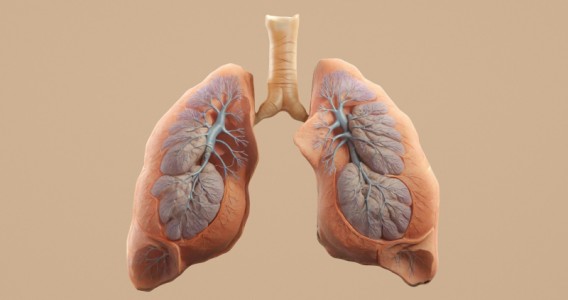

Obesidad e inflamación pueden acelerar el envejecimiento de los pulmones y aumentar el riesgo de EPOC

Un estudio con casi 900 adultos indica que, aunque el tabaquismo sigue siendo el principal factor de riesgo para la pérdida de la función pulmonar, la inflamación sistémica y la obesidad también aumentan el riesgo de desarrollar enfermedad pulmonar obstructiva crónica